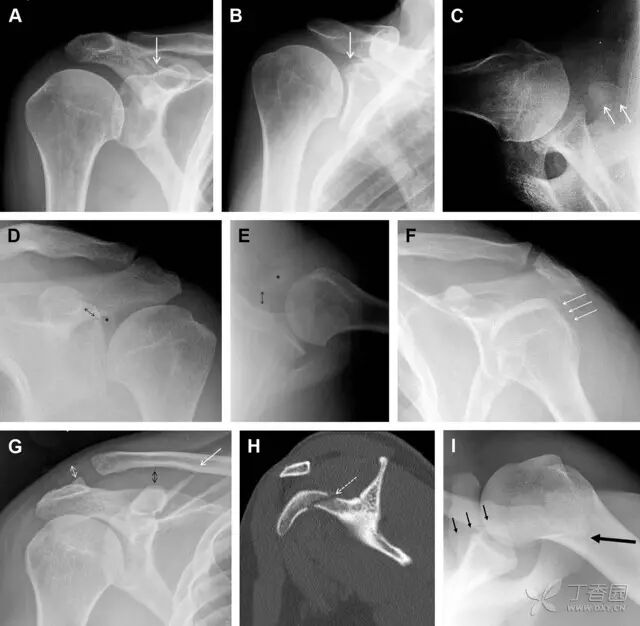

23 单纯肱骨大结节骨折

与其它肱骨近端骨折不同,单纯肱骨大结节骨折常发生于年轻人。肱骨大结节骨折常由撞击或剪切/撕脱损伤所致:

撞击包括直接撞击、肩峰撞击、上关节盂撞击(极度外展时);

剪切/撕脱损伤常发生于肩关节前脱位。

在常规前后位片上,大结节与肱骨头重叠,骨折不易发现,外旋位前后位片有助于诊断。

图 1 大结节骨折。(A)脂肪抑制序列斜冠状位 MRI,显示肱骨大结节线性骨折无移位(箭头)与周围骨水肿;(B)外旋位前后位(AP)片,证实大结节骨折(箭头),典型的骨折愈合过程中的骨吸收表现;(C、D)初诊时内旋位、外旋位前后位片,初诊时漏诊,仔细回顾影像,内旋伞下可见双密度影(椭圆),骨皮质中断(箭头)

肩胛骨几何形状复杂,受到邻近其它骨性结重叠阻挡,且肩胛骨骨折少见,因此容易漏诊。当存在解剖变异时,诊断更为困难。

图 3 肩胛骨骨折正侧位片:由于骨块的叠加,(A)前后位片示「V」形高密度影(*),肩胛颈下方可见骨皮质碎片(箭头);(B)侧位片示骨皮质中断,骨折段移位,但由于肱骨的重叠遮挡,决断往往比较困难

喙突骨折可发生于直接暴力、肩关节脱位过程的肱骨头撞击、以及撕脱骨折(肱二头肌短头、喙肱肌)。

其中喙突基底部骨折最多见,常发生于直接暴力或肱骨头前脱位,骨折可延伸至关节盂。

而撕脱骨折多为喙突尖部的骨折。需要加拍腋位和 Stryker 位片(X 射线束以喙突为中心并头倾 10°,手臂外展,这样可以避开骨性结构的阻挡)。

有时,负重位片可发现并存的肩锁关节脱位,将有助于诊断。

图 4 喙突骨折。66 岁男性患者,射击后右肩前方疼痛。(A)内旋位前后位片投影隐约可见喙突基底部骨折(白色箭头),(B)外旋位前后位片投影结构存在重叠,(C)腋位投影时可良好显示。(D~F)喙突骨折伴 Hill-Sachs 损伤:肩关节脱位后慢性疼痛,喙突骨折块(*)向前外侧移位(双箭头),在外旋前后位(D)及腋位(E)片上均可显示,在内旋位前后位(F)片上,喙突被遮挡,但可见肱骨头 Hill-Sachs 损伤。(G、H)喙突骨折伴肩锁关节脱位,肩锁关节分离(白色双箭头),而喙锁间距正常(黑色的双箭头),应警惕喙突骨折。(I)喙突与肩峰骨化中心:对于未成年人,喙突与肩峰骨化中心可同时存在,易与骨折混淆,此时,拍对侧的 X 线片对比将有助于诊断。

肩峰骨折为高能量损伤,多由直接暴力导致,好发于中青年患者,多伴有肩关节其它结构损伤。有必要拍摄 Rockwood 位(前后位片,X 线束尾倾),特别有利于显示肩峰下部及肩峰下间隙。

图 5 肩峰骨折。内旋位前后位(A)片上,骨折线几乎被喙突完全遮挡, 但是在标准前后位(B)和腋位(C)片上可见骨折线